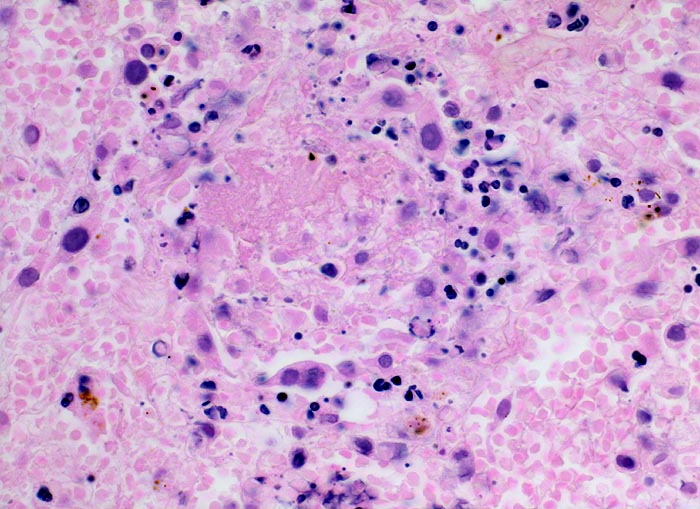

• Alveolen gefüllt mit zerfallenden Erythrozyten, Kerntrümmern und Fibrin.

• Lungengerüst erhalten im Randbereich der Nekrose, nicht mehr erkennbar im Zentrum.

• Abgeblasste Zellkerne in der Nekrosezone.